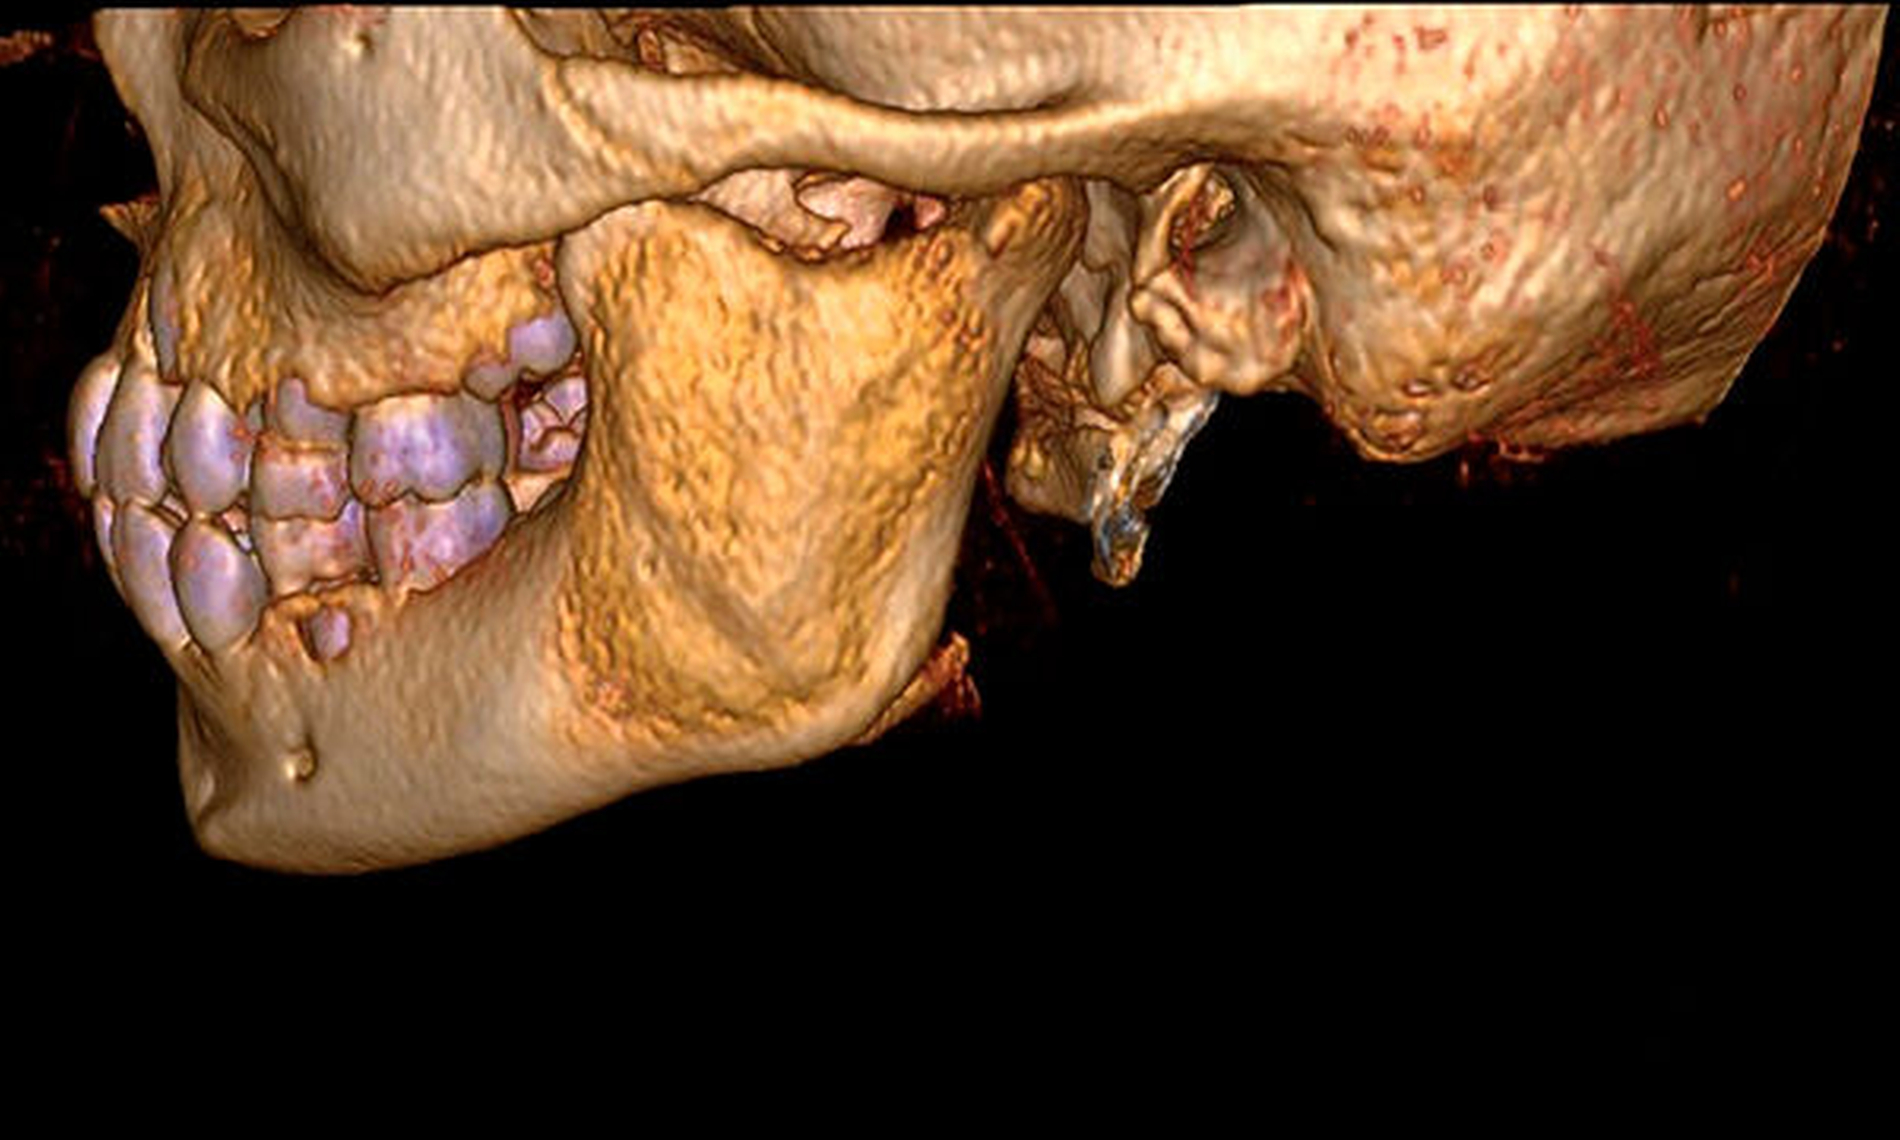

Zur (differenzial-)diagnostischen Beurteilung und Darstellung der Befundausdehnung wurde zunächst unter Berücksichtigung des Kindesalters eine Bildgebung mittels Magnetresonanztomografie (MRT) durchgeführt. Diese zeigte in der T1-Wichtung im Bereich des linken Kieferwinkels lokalisierte diffuse, inhomogene und signalarme Strukturen mit expansiver Auftreibung der Kortikalis und entzündlicher Begleitreaktion der angrenzenden Muskulatur (Abbildung 1). Aufgrund der MRT-morphologisch nicht zweifelsfrei wegweisenden Befunde erfolgte zur genaueren Beurteilung des knöchernen Gesichtsschädels eine ergänzende Computertomografie (CT), die kongruent zu den signalarmen Bereichen in der MRT milchglasartige Volumenvermehrungen des linken Kieferwinkels mit Ausbreitung in den Processus coronoideus und ins angrenzende Collum mandibulae aufwies (Abbildung 2). Die durchgeführte CT stützte bei den oben genannten, charakteristischen Kriterien (Abbildung 3) im Kontext der klinischen Befunde die Arbeitsdiagnose der fibrösen Dysplasie.

Neben der klinischen Untersuchung ist die Diagnose der fibrösen Dysplasie überwiegend radiologisch zu stellen [Vogelsang et al., 1978]. Typischerweise zeigt eine fibröse Dysplasie bildmorphologisch in Orthopantomogramm (OPTG) und CT neben einer ausgedünnten, intakten Kompakta eine charakteristische, milchglasartige Struktur der betroffenen Knochen [Fitzpatrick et al., 2004]. Abhängig davon, ob fibröse oder ossäre Gewebeanteile überwiegen, dominieren Aufhellungen oder Verschattungen die oben genannten bildgebenden Verfahren. Insbesondere zur besseren Differenzierung, respektive Abgrenzung mon- und polyostotischer Krankheitsbilder ist in ausgewählten Fällen auch eine nuklearmedizinische Skelettszintigrafie wegweisend [Vogelsang et al., 1978]. Neben klar kennzeichnenden radiologischen Merkmalen kann auch der Nachweis einer GNAS-Genmutation die herkömmliche chirurgische Biopsiediagnostik, deren Notwendigkeit immer in Abhängigkeit des zu erwartenden diagnostischen Nutzens und des individuell bestehenden Frakturrisikos evaluiert werden sollte, ergänzen [Ostertag und Glombitza, 2018].